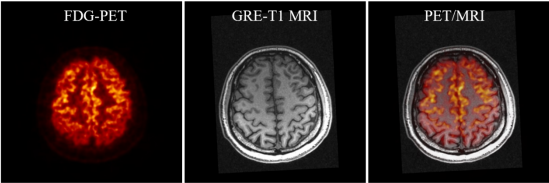

SIAT bPET和联影uMR790 3T磁共振成像系统上同时取得的人脑PET/MRI图像

杨永峰介绍道,与国外商业磁兼容脑PET成像仪器相比,SIAT bPET的效率提高了近2倍(从7.2%到14%),平均体分辨率提高了30倍以上(从约64mm3到2mm3)。同时,SIAT bPET采用了创新的电子学和磁兼容设计,使得磁共振成像对PET成像的影响几乎可以忽略不计,PET成像对磁共振成像图像信噪比的影响小于5%,满足同时召开PET/MRI成像的尖端科研需求。